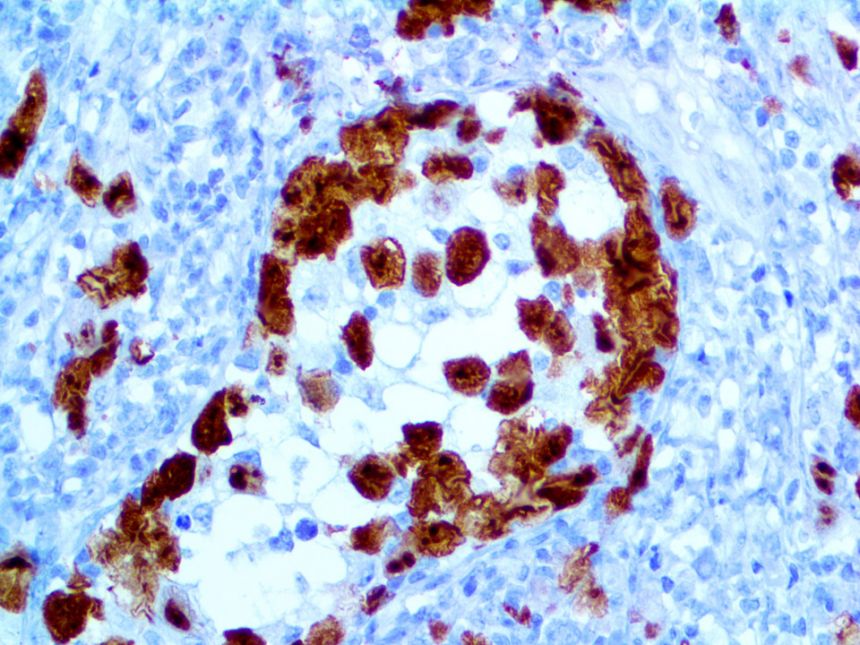

It is the ICU physician who is most likely to witness one of the deadliest manifestations of the abnormal immunological response, the cytokine storm syndrome (CSS). This response is also referred to by some as the cytokine release syndrome (CRS). CSS is characterized by continuous activation and expansion of macrophage and lymphocyte populations, which secrete large amounts of cytokines, causing the cytokine storm. This massive cytokine release is akin to hemophagocytic lymphohistiocytosis (HLH) disease, a syndrome characterized by initial unchecked and persistent activation of cytotoxic T lymphocytes and NK cells.

Clinical and laboratory manifestations of HLH include fever, enlarged liver and/or spleen, neurologic dysfunction, coagulopathy, liver dysfunction, cytopenias (i.e., low levels of erythrocytes, leukocytes, and/or platelets), hypertriglyceridemia, hyperferritinemia, hemophagocytosis, and eventually diminished NK cell activity as the immune system becomes progressively paralyzed. HLH can be familial (primary HLH) or secondary to another disease process (sHLH), such as rheumatic disease, in which it is referred to as macrophage activation syndrome (MAS, characterized by elevated ferritin).